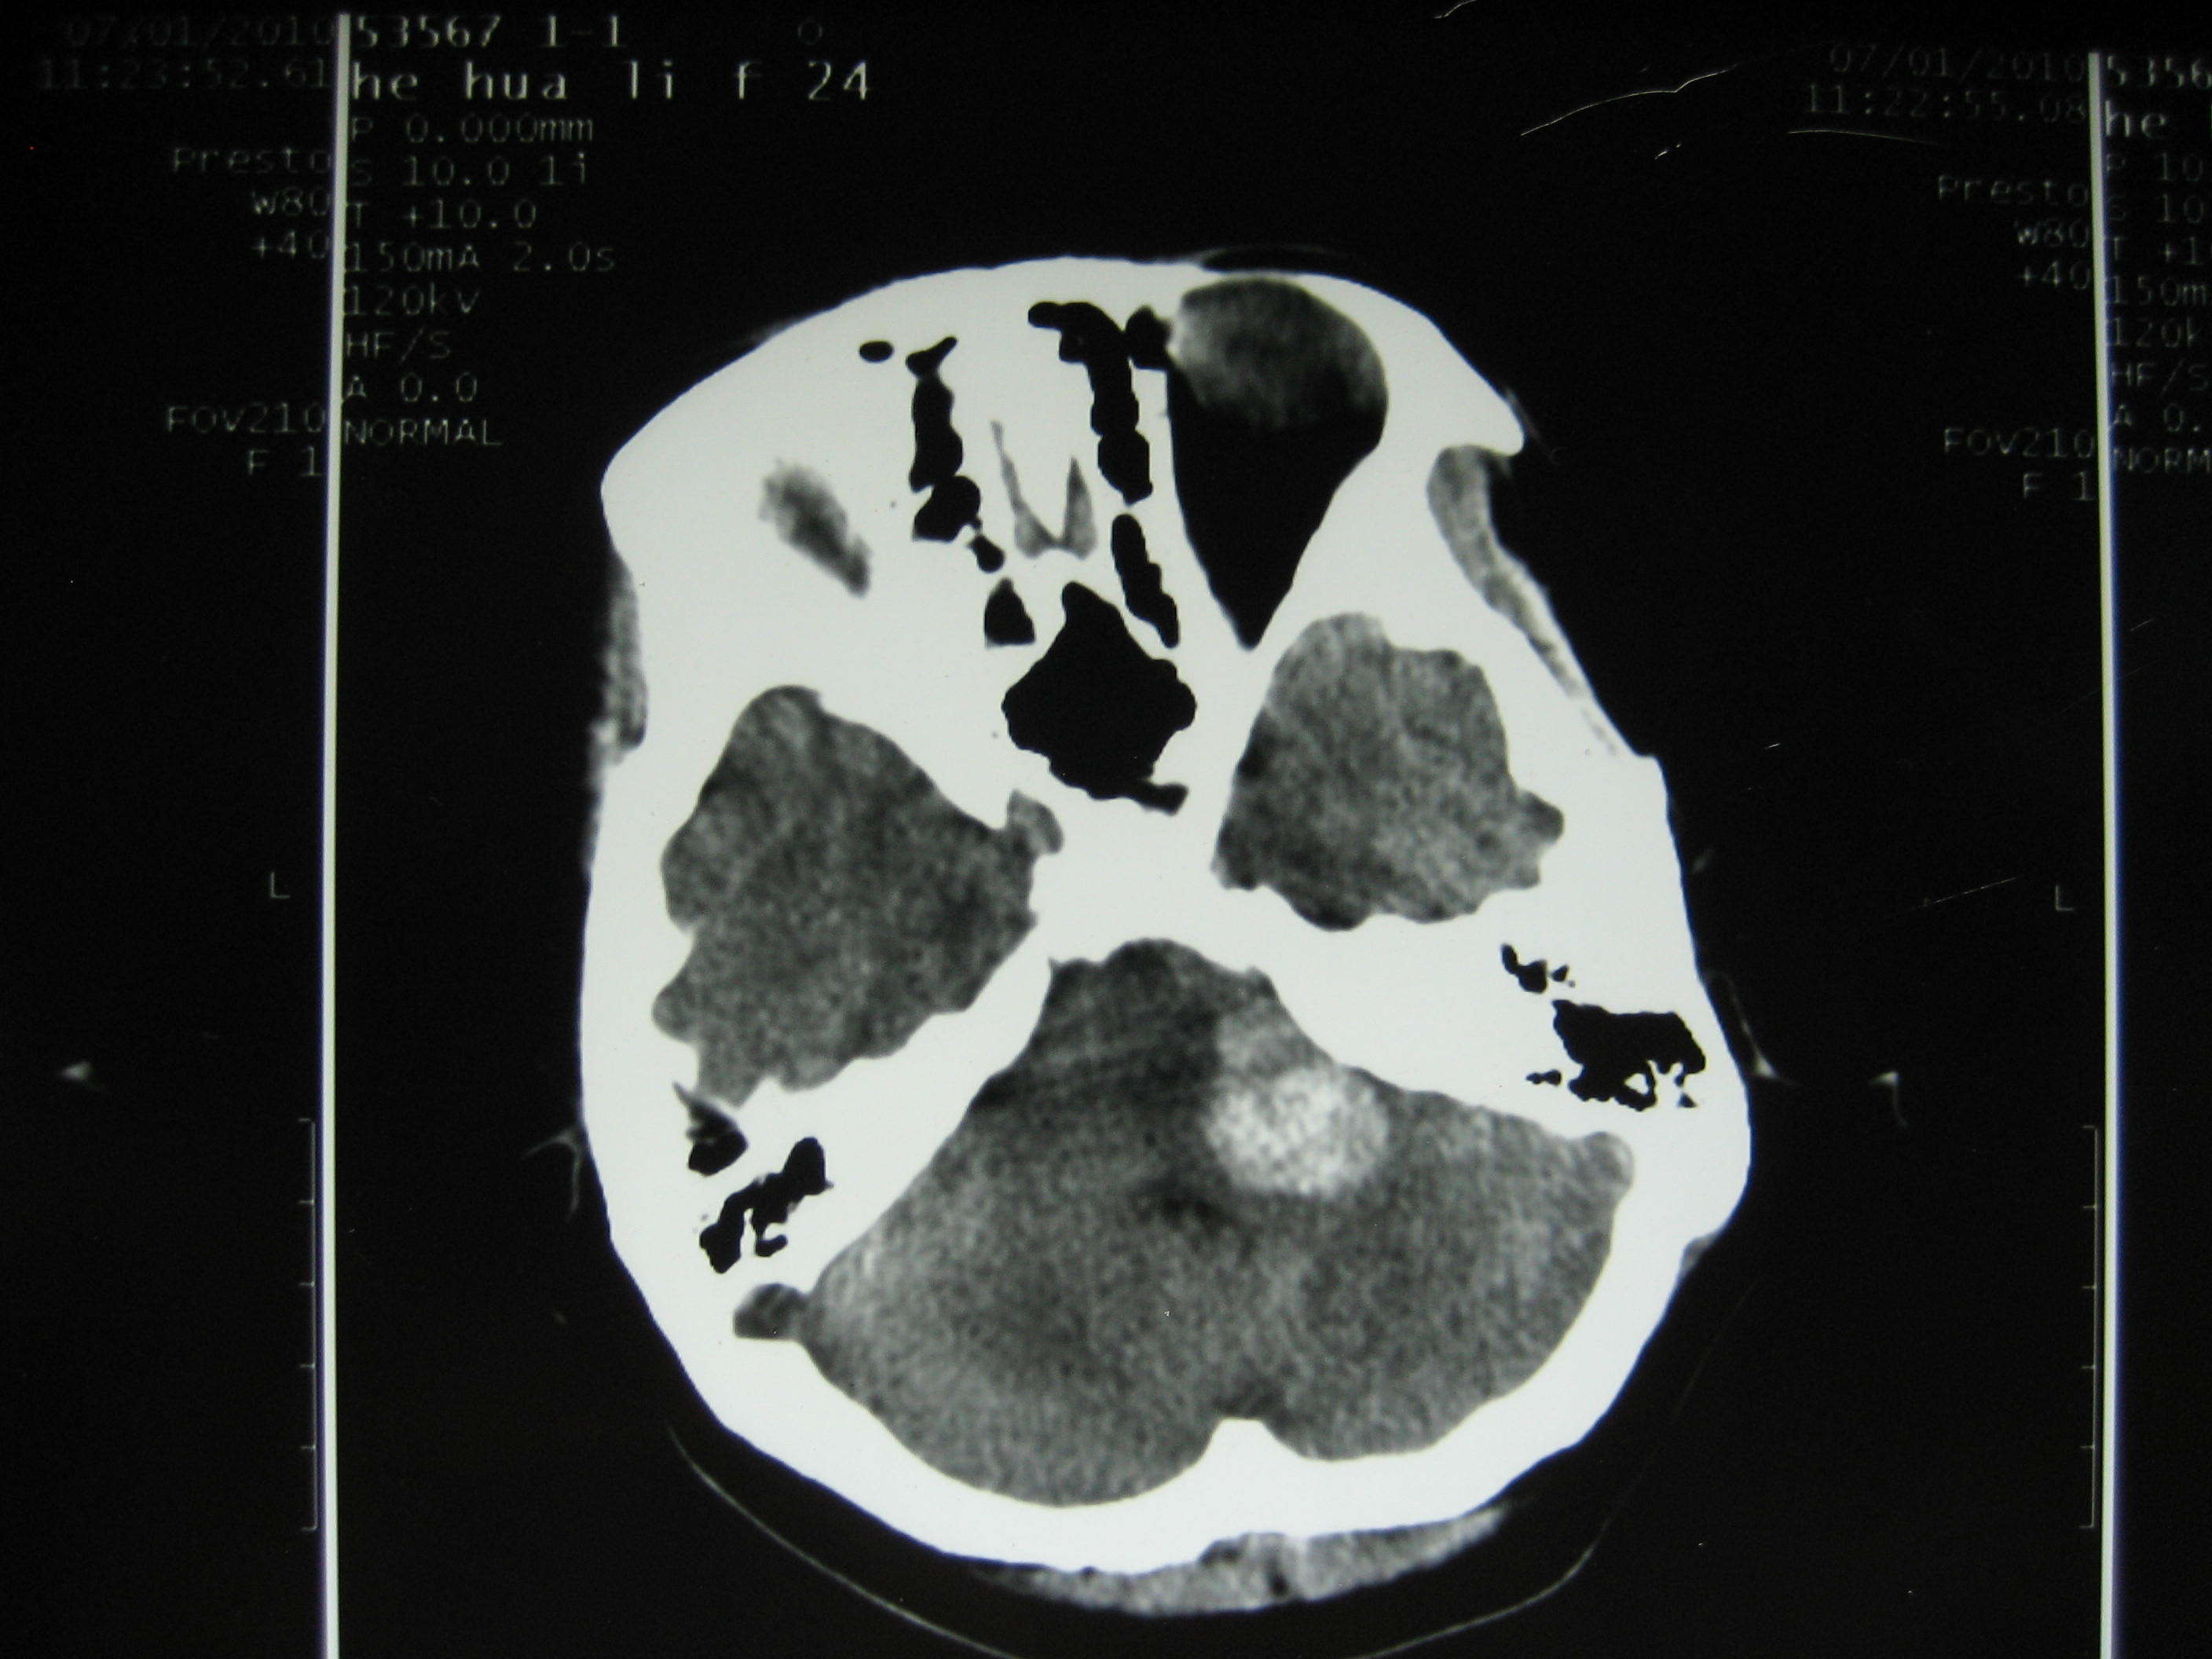

于2019-04-08行颅内动脉瘤切除术及颅外-颅内血管搭桥术,术后患者神清